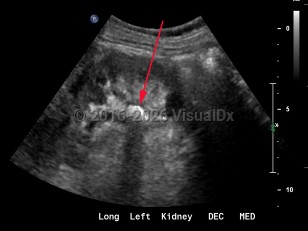

Polycystic kidney diseasePolycystic kidney disease